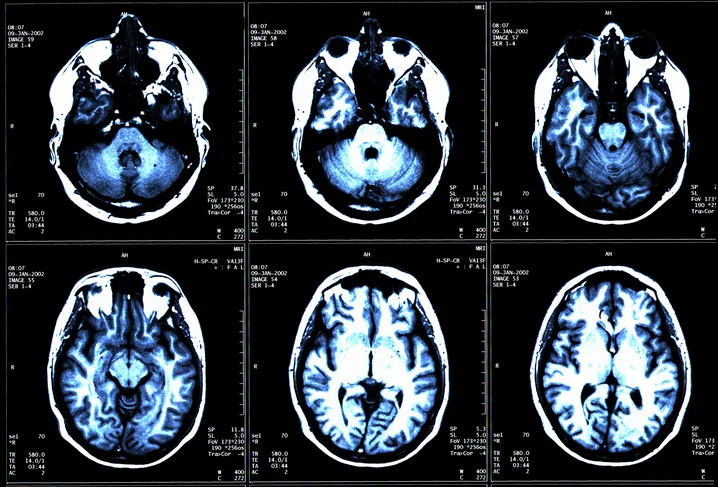

Only doctors can diagnosis MS but it’s not easy. There is no single test for MS available yet to verify or rule out MS; however magnetic resonance imaging (MRI) is proving valuable in helping reach a definitive diagnosis. This along with diagnostic criteria that incorporate MRI findings have been developed and revised by experts in the field giving new hope in helping clinicians in making an accurate and timely diagnosis.